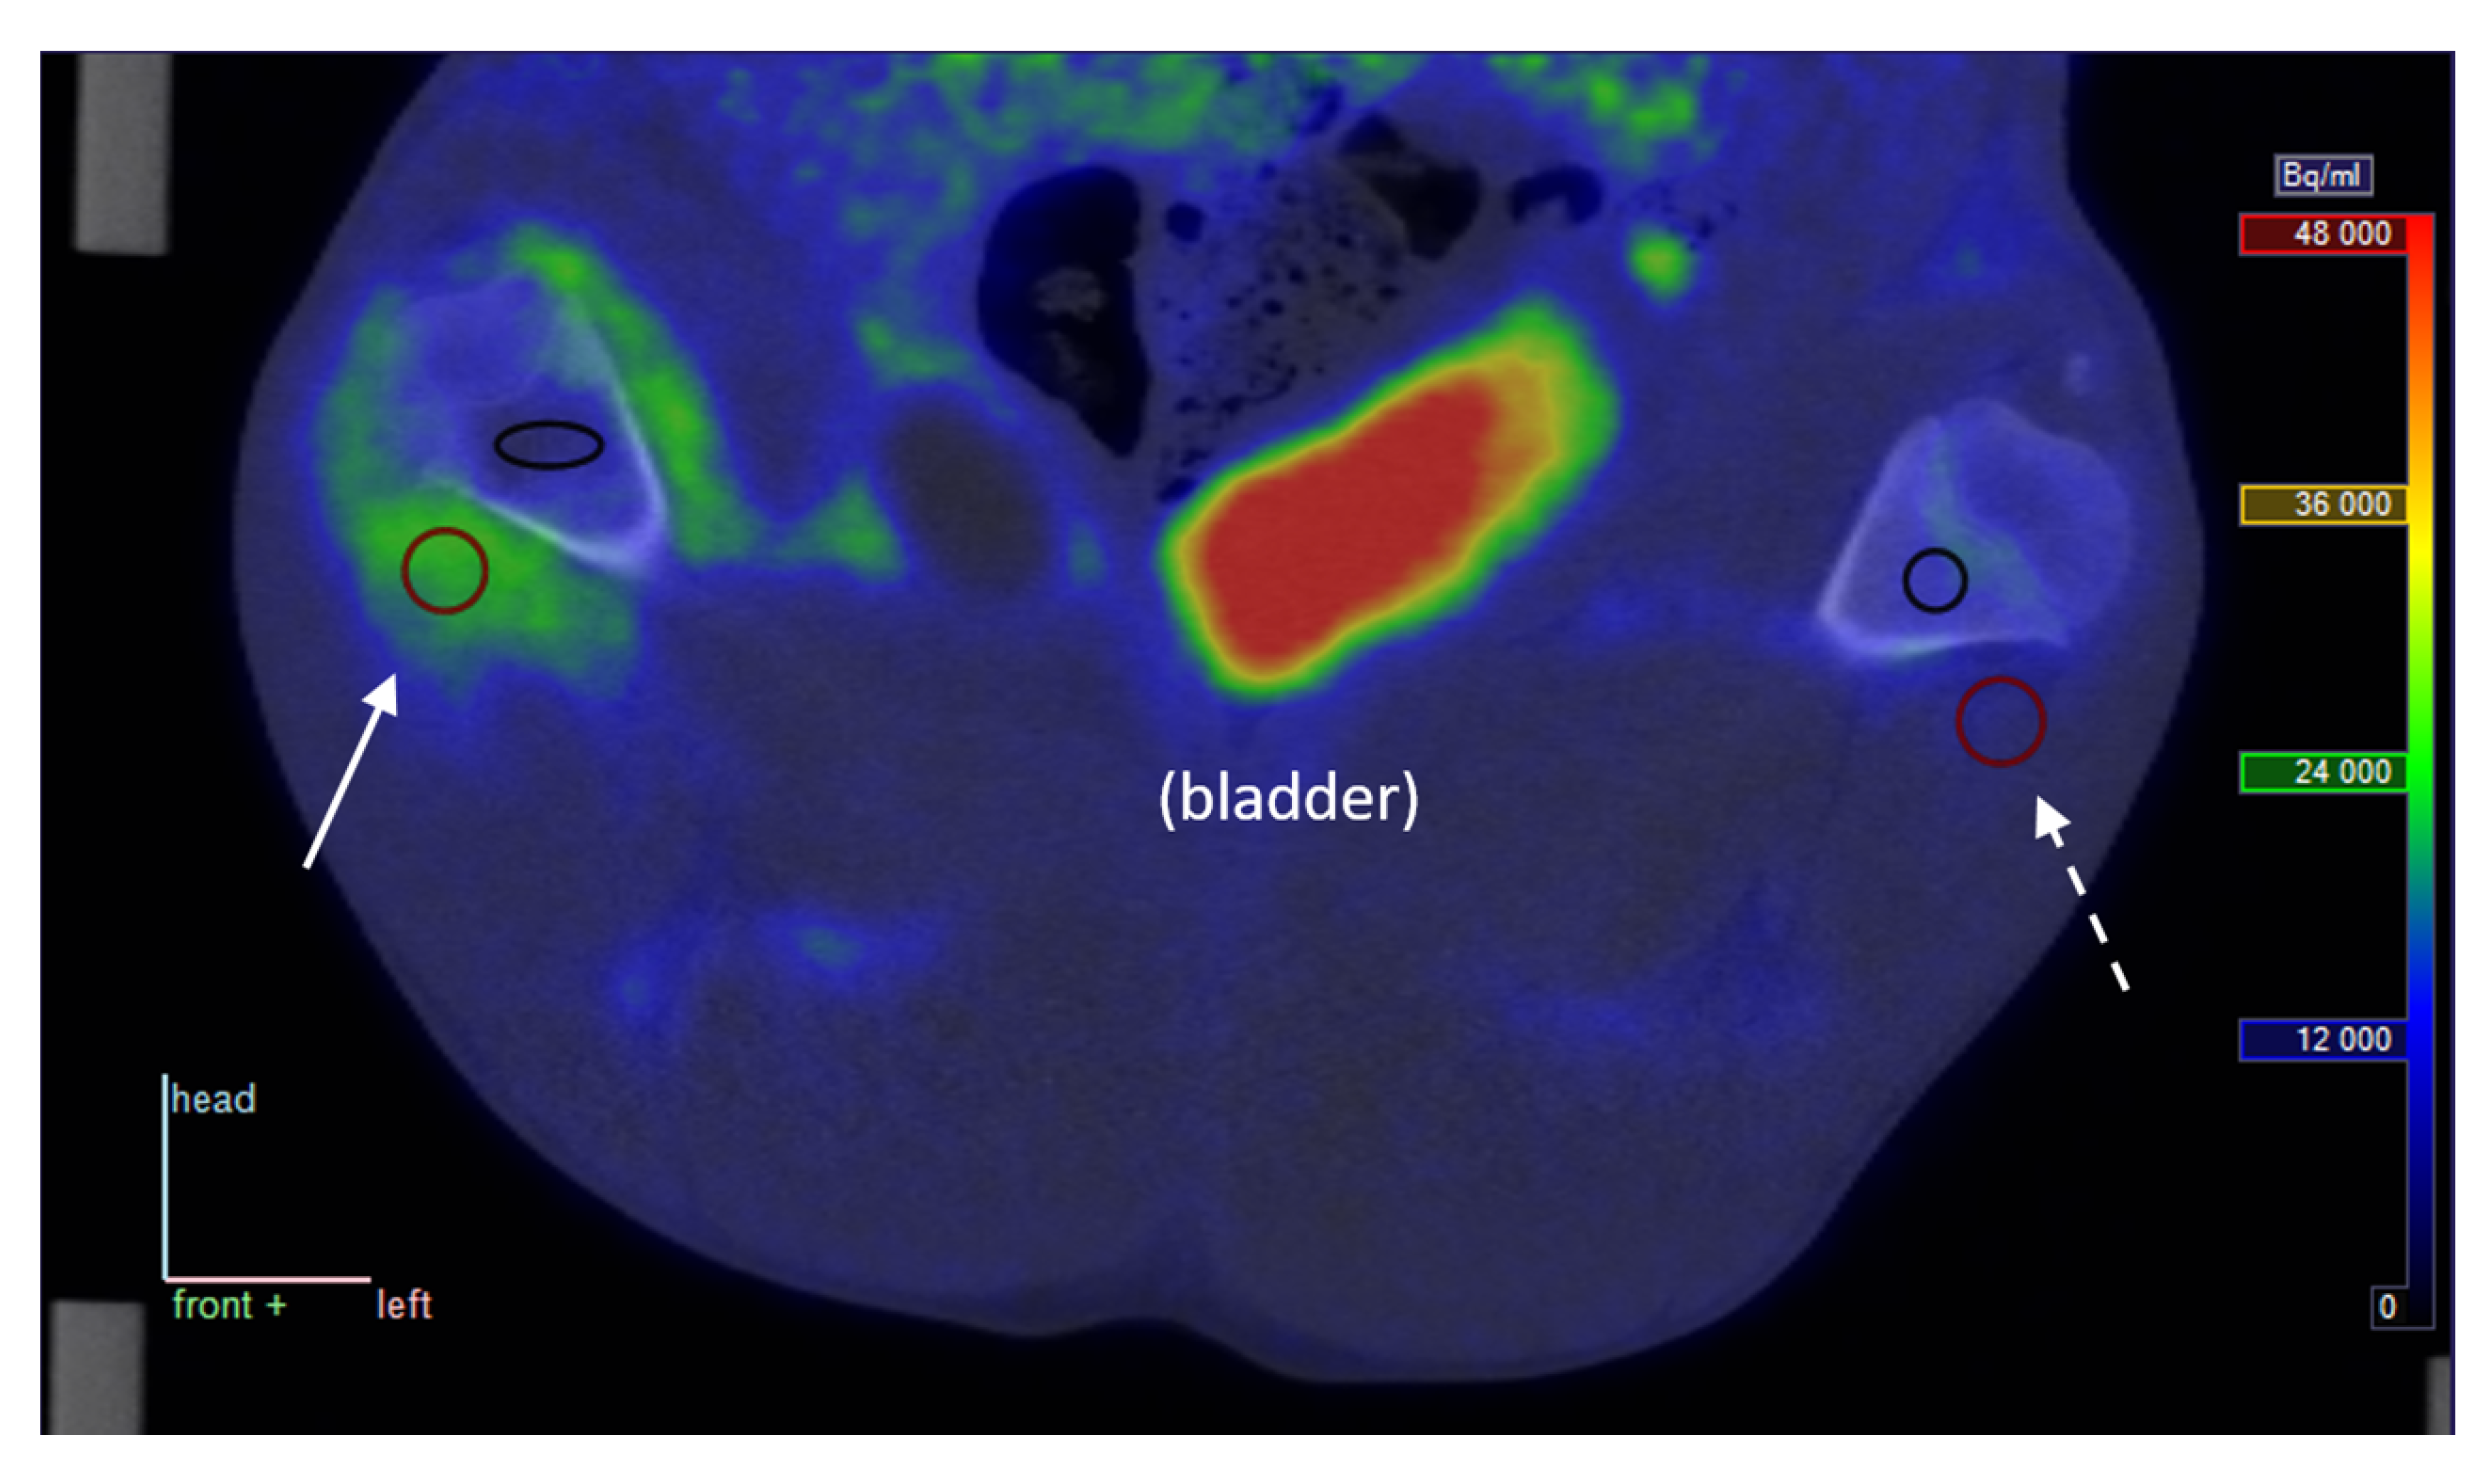

Visually, [68Ga]Ga-DOTA-Siglec-9 showed elevated uptake in inflamed and infected soft tissues, while not being prominent in infected bone (osteomyelitis). As an example, a coronal view of the uptake around the femur in pig no. 25 is shown in Figure 1.

Representative PET/CT image from pig no. 25. The pig was lying supine with roughly upward-pointing limbs, and the view is coronal, seen from the ventral side of the animal (“front” = opposite of back is in the direction of the reader); the top of the image is in the direction of the animal’s head. Full arrow: Uptake in phlegmon/early abscess at the right distal femur. Dotted arrow: Similar non-infected tissue for comparison. Red circles show sections of volumes of interest (VOIs) in soft tissue, black ellipse/circle show VOIs in bone tissue. The PET image represents the summed data from 15 to 30 min post-injection (p.i.). The tissue samples presented in Figure 3 were taken from positions approximately corresponding to the soft tissue VOIs.

At late time points, the decay-corrected PET signal was markedly reduced in all tissues outside the bladder, indicating that uptake of the tracer is reversible rather than irreversible (see Figure 2).

In summary, [68Ga]Ga-DOTA-Siglec-9 shows increased uptake in infected (and inflamed) soft tissue compared with control tissue; however, this study fails to demonstrate elevated uptake in infected bone (osteomyelitis). These quantitative results correspond to the visual impression of the sample image in Figure 1, where increased uptake is clear in infected soft tissue but not in the infected bone (cf. with pig no. 25 in Table 2 and Table 3). Note, however, that this comparison is partly qualitative. The determination of VT on a reliable absolute scale will depend on improved knowledge on the nature of the radioactive metabolite products of [68Ga]Ga-DOTA-Siglec-9. The moderate correlation between SUV and VT indicates that the volume of distribution gives information that is not just a complicated version of the SUV.